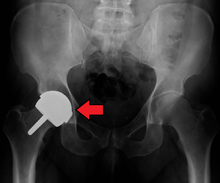

Dislocation

Dislocation is the most common complication of hip replacement surgery. At surgery the femoral head is taken out of the socket, hip implants are placed and the hip put back into proper position. It takes eight to twelve weeks for the soft tissues injured or cut during surgery to heal. During this period, the hip ball can come out of the socket. The chance of this is diminished if less tissue is cut, if the tissue cut is repaired and if large diameter head balls are used. Surgeons who perform more of the operations each year tend to have fewer patients dislocate. Doing the surgery from an anterior approach seems to lower dislocation rates when small diameter heads are used, but the benefit has not been shown when compared to modern posterior incisions with the use of larger diameter heads. Patients can decrease the risk further by keeping the leg out of certain positions during the first few months after surgery. Use of alcohol by patients during this early period is also associated with an increased rate of dislocation.